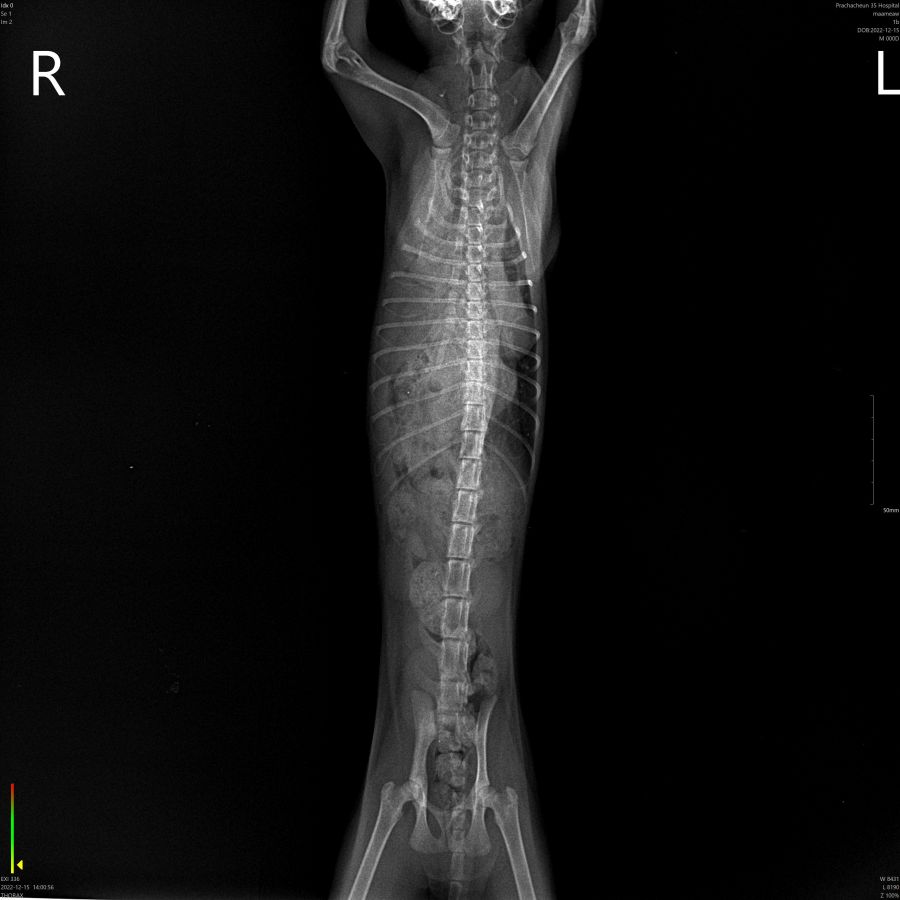

สวัสดีค่ะ ต้องการขอระดมทุนรักษาแมวจรชื่อ นุ่มนิ่ม (ชื่อน้อง เราตั้งเองหลังจากที่เจอน้องค่ะ) เจอครั้งแรกวันที่ 12 ธันวาคม 2565 เวลาประมาณ 4 ทุ่ม น้องมีอาการหายใจแรงเหมือนหอบ เช้าวันต่อมาก็เลยรีบติดต่อสัตวแพทย์แถวบ้าน และนำไปไว้ที่คลีนิคในวันนั้นเลยเวลา 10:30น. หมอขอดูอาการแล้วจึงนำน้องไปเอ็กซเรย์ที่โรงพยาบาลสัตว์ประชาชื่น ผลคือมีเนื้อเยื่อฉีกขาดทำให้ลำไส้ไหญ่ไหลเข้าไป (ตามฟิล์ม X-ray ที่แนบ) ต้องผ่าตัดจึงจะหาย แต่ค่าใช้จ่ายสูงมาก  และยังมีค่าใช้จ่ายที่ต้องอยู่รพ.ต่ออีกหลายวัน เพราะเนื้อเยื่อที่ฉีกขาดค่อนข้างเยอะและผ่าตัดยาก จึงจะขอระดมทุนช่วยเหลือแมวจรตัวนี้ หากหายดีแล้ว เราจะรับเลี้ยงต่อเองค่ะ